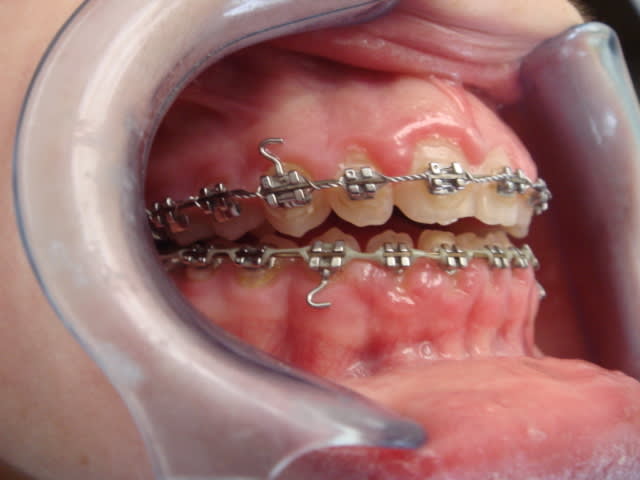

De toute facon il est claire que ce cas presente une dysfonction linguale et je ne sais pas si cela etait pris en charge par l'orthodontiste precedent ou pas, c'est un probleme qu'il faut regle. La chainette est dramatique pour l'hygiene et cela aussi doit etre pris en consideration. Un point tres important c'est de savoir si cette beance etait la avant de commencer ou s'est cree pendant le traitement et a quel moment. Personellement je trouve aussi que la solution proposee par le nouvel orthodontiste n'est pas la meilleure, je serai tente par une FEO occipitale ( appui vertical ) afin de reduire la classe II, redresser le plan occlusal et provoquer une autorotation de la mandibule ce qui va reduire la hauteure verticale anterieure et ameliore la musculature labiale et peri orale car sur la photo il y a une tension quand meme.. Ceci est mon avis a premier vu mais les radios peuvent confirmer ceci ou pas. Bon courage

La langue est vraisemblablement en position basse.

Elle se met là ou il y a de la place, la pauvre !

La chaînette élastique a lingualé les Inc. Inf. et le profil reste tendance prognathe.

Une extraction des P.M. sup semble donc contre indiqué.

Cette Cl.II. semble être une Cl. 1.5

Il faudrait plutôt un reformage et une avancée du Max. Sup. pour faire la place à la langue.

Pendant ce reformage, on pourra alors faire, avec des chances de succès, une rééducation de langue à laquelle on proposera une nouvelle enveloppe.

Tu veux avancer le maxillaire alors tu es en classe II ???? Tu dis que la langue est en position basse tandis que la beance totale est generalement signe d'une interposition laterale et anterieure moyenne de la langue.

Bref revenons au cas, d'apres la radio je trouve que la beance etait la avant de commencer et cela n'a pas ete pris en charge pendant la premiere partie du traitement!!! Donc il faut le faire maintenat au plus vite. La FEO a traction verticale c'etait mon idee et je la maintiens pour basculer le plan bispinal et favoriser une rotation anterieure de la mandibule ce qui corrige la classe II et reduit la beance. C'est une FEO de controle vertical du plan occlusal et non pas une force orthopedique. Il faut prendre les 7 aussi si cela n'a pas ete fait. Les elastiques de classe II dans une typologie aussi defavorable risque d'aggraver la tendance verticale et ce qu'on peut gagner sagittalement on le perd verticalement. A mon avis cela peut etre necessaire a la fin pour parfaire la classe I.